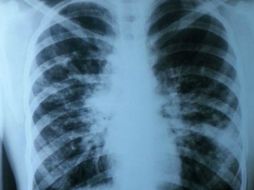

Suplementos Cáncer de pulmón tiene un alto índice de mortandad 28 de abril de 2016 - 08:50 hs IMSS Calor de hogar

Suplementos Dolor de pecho y debilidad, síntomas de cáncer de pulmón 10 de octubre de 2015 - 07:22 hs Enfermedades Calor de hogar